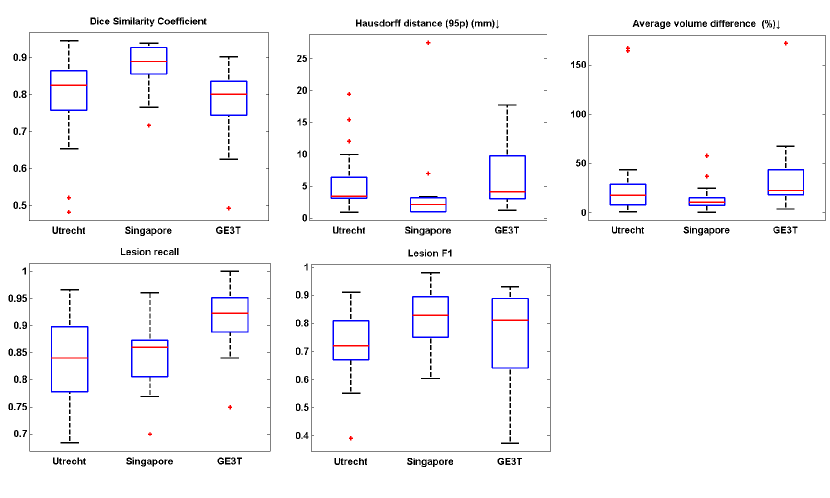

Figure 7 plots the distributions of segmentation performances on cases from each scanner being tested in turn, with each sub-figure showing performances using one of the five metrics. In general, for every 20 cases from each of the three testing scanners in the cross-scanner evaluation, the segmentation result between each other was comparable, showing our system is robust to unseen scanners. It could be observed that the segmentation performance on dataset GE3T was relatively poor. This could be explained that the voxel size of cases in GE3T has a significant difference from that captured by two other scanners. Combination of modalities will be discussed in Section 5.3 Table 6 compares the segmentation performances of the top performing teams on two unseen scanners. Our method achieved, on average, the best Dice similarity coefficient and lesion recall of 74.5% and 87% respectively and runner-ups on other three metrics.